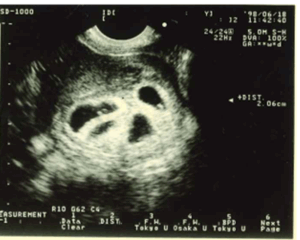

渡邉さんは、約3年半の不妊治療の末に妊娠。最初に確認されたのは4人の胎児で、医師からは「リスクが高いため、妊娠を続けるか1週間以内に決めてください」と告げられました。

その後の検査で、胎児はまさかの5人に。しかし医師からのフォローもあり出産に踏み切りました。